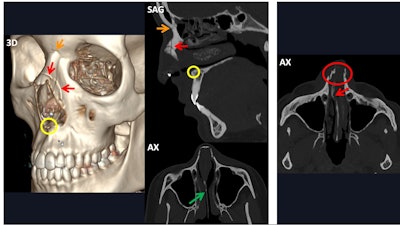

Bilateral frontal fracture involving both the anterior and posterior wall of both frontal sinuses (3D and red arrows). The fracture spreads inferiorly to both superior orbital rims (magenta arrows), posteriorly towards the anterior cranial fossa, with a resulting pneumocephalus bubble (blue arrow), and medially (yellow arrow in the axial view). Nevertheless, both frontonasal ducts remain intact (yellow arrows in sagittal views). AX = axial view, COR = coronal view, SAG = sagittal view, 3D = volume-rendered reconstruction. All figures courtesy of Dr. Mónica Régil Guerrero et al and presented at ECR 2025.

“The most commonly fractured structure in the frontal bone is the anterior wall of the frontal sinus, followed by both the anterior and posterior walls,” they stated. “Whenever the posterior wall alone is fractured, the skull base and cranial vault should be examined, as they could harbor the source fracture.”

Frontal fractures can occur in three ways:

- Inferiorly: The superior orbital rim will be involved.

- Medially: The frontonasal duct should be checked because this is the drainage tract of the frontal sinus into the nasal cavity, through the middle nasal meatus; when this is fractured, a mucocele can arise.

- Posteriorly: The anterior cranial fossa is immediately behind the frontal bone; therefore, cerebrospinal fluid leak, encephalocele, pneumocephalus, and traumatic or infectious intracranial complications may occur.